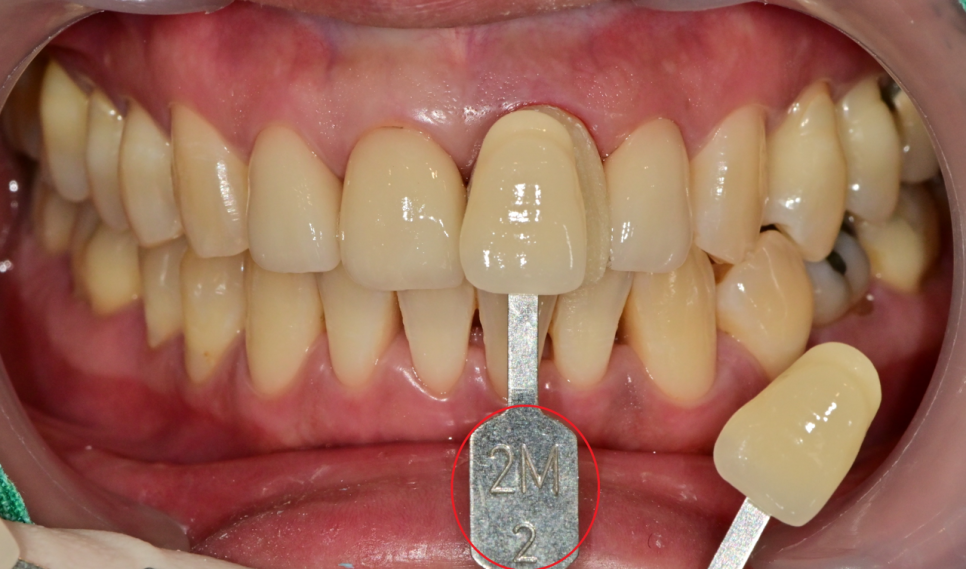

빨간색 동그라미는 치아의 색상을 카테고리화 시킨 것인데

shade guide란것을 이용하여 최대한

주변 치아와 맞는 색을 찾으려 노력을 해봤습니다.

미백에서도 쓰여지고, 심미적인 치료를 할 때는 자주 이용하는 도구입니다.